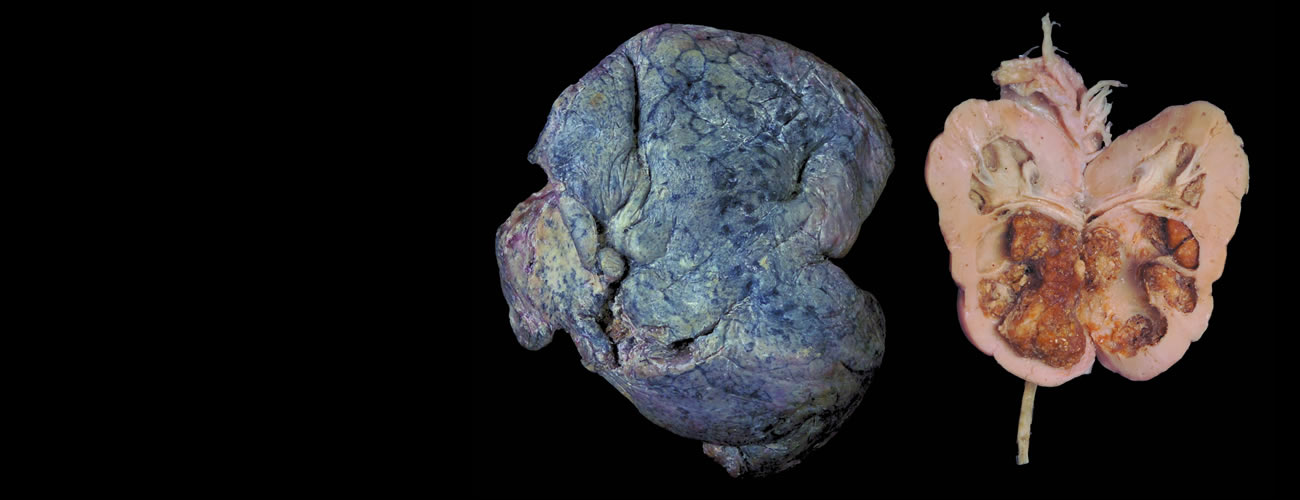

捐献遗体的主要用途:

1.医学教育,为91吃瓜捐赠人体教学标本,培养学生敬畏生命的品质和增强实践能力;

2.医学研究,能进一步分析、研究疑难病症,总结经验,提高诊断水平。